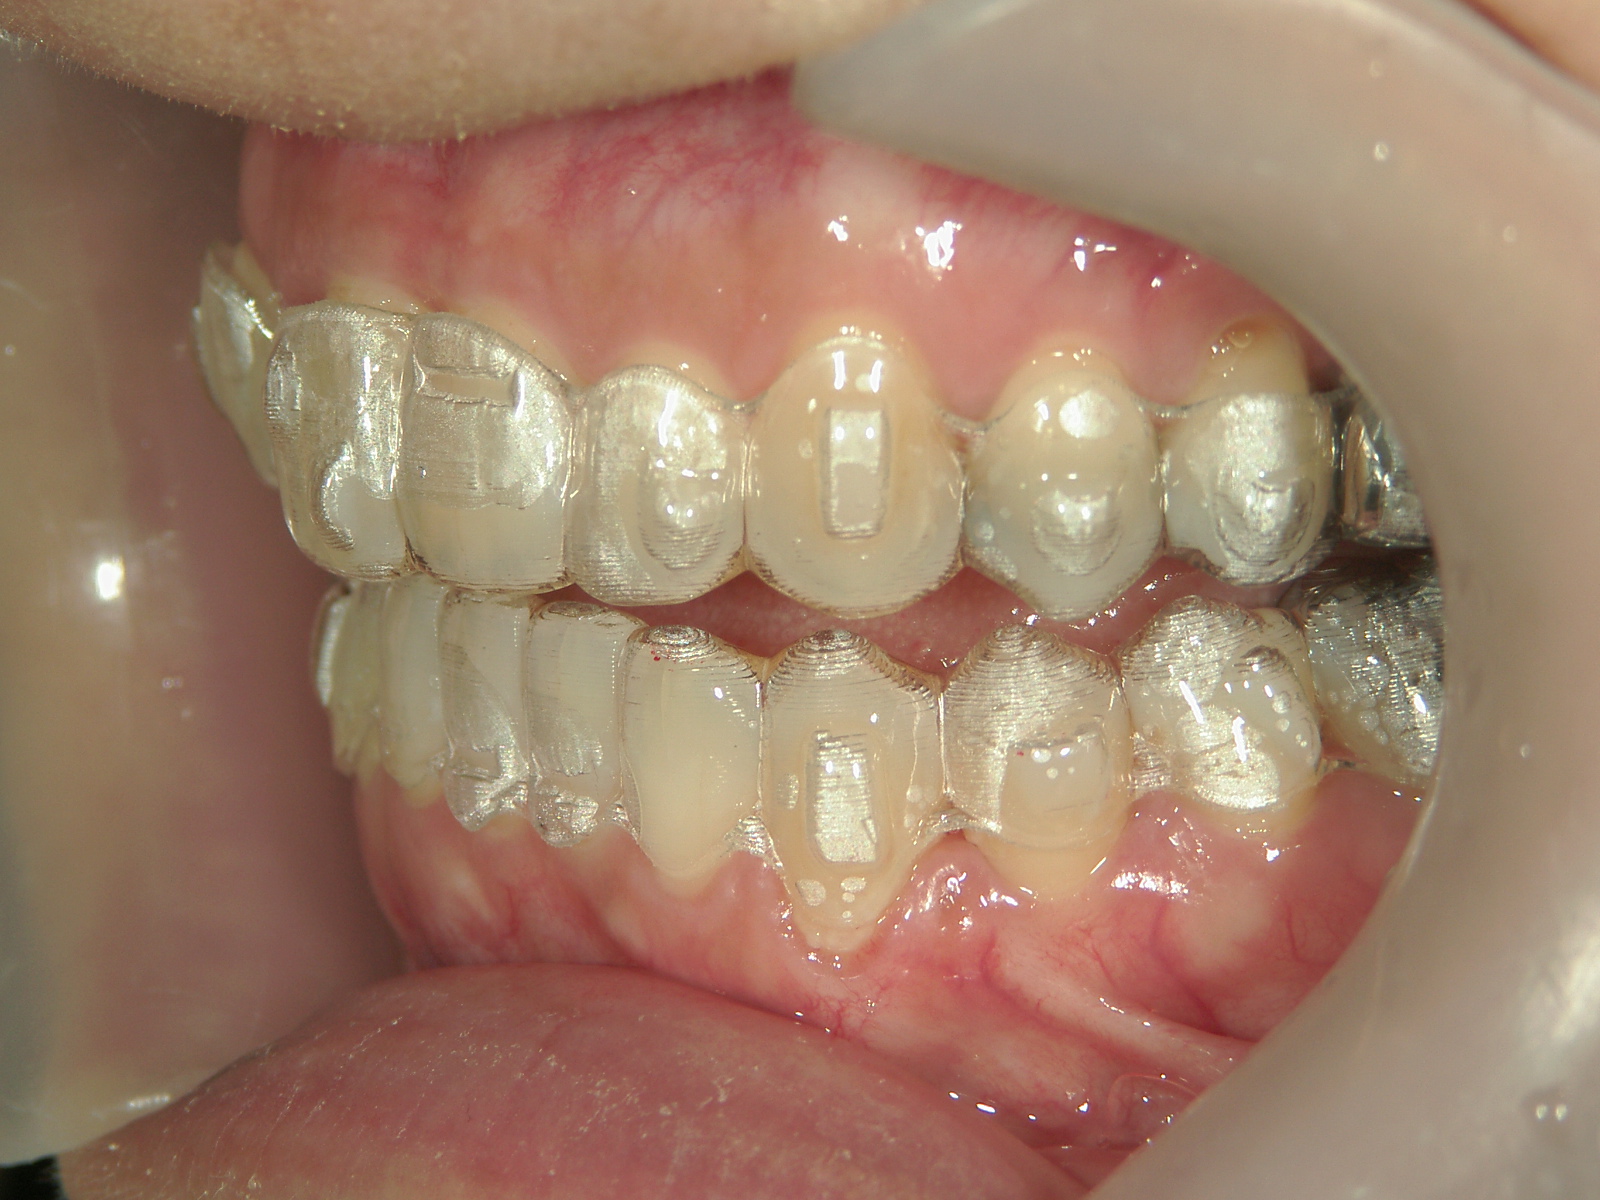

①患者様はインビザライン矯正をご希望でしたが、上顎骨が小さく、受け口になっているので、インビザライン矯正で治療するために「骨切断OPE」「矯正装置(MSE+フェイスマスク)」で上顎骨を拡大しました。

②右上前歯が内側に入っているため、歯列に入る隙間を作るためにワイヤー矯正を併用し、右上前歯を出しました。

③矯正装置を除去し、インビザライン矯正で歯列を整えました。